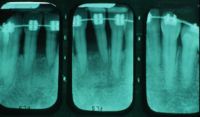

La evidencia clínica de una enfermedad periodontal grave fue respaldada por las pruebas radiográficas en las que se observa una pérdida de hueso de más del 70% en los incisivos mandibulares y la presencia de un grado de movilidad 2 para los cuatro incisivos.

Las radiografías de la férula acabada verifican la unión de los incisivos con periodontitis.

Otro factor que complicaba el caso fue que el paciente había completado dos años de tratamiento de ortodoncia para cerrar el espacio que existía en anteriores debido a la pérdida de un incisivo central por enfermedad periodontal. Hay evidencia radiográfica de pérdida de masa ósea de más del 70% en el incisivo central restante.

Desde un punto de vista incisal la férula tiene un volumen mínimo. Las radiografías de la férula acabada verifican la unión de los incisivos con periodontitis. La radiografía muestra como la fibra está incrustada en el composite.